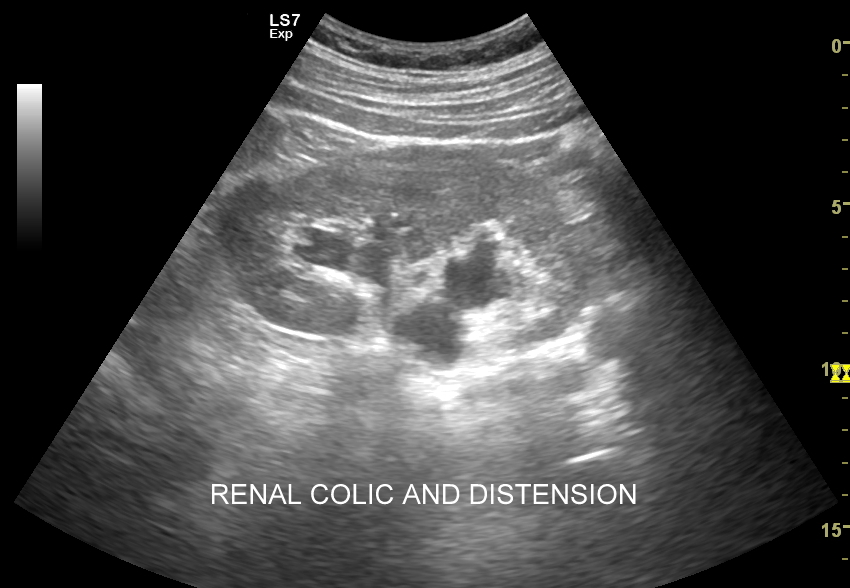

Kamica nerkowa może być bezobjawowa. W długotrwałym, przewlekłym przebiegu może prowadzić do niewydolności nerek. Z kolei w formie ostrej objawia się jako kolka nerkowa lub niecharakterystyczne pobolewania.

Objawy kolki nerkowej wynikają z mechanicznego drażnienia i wtórnego ranienia ścian moczowodu w trakcie przemieszczania się kamienia, a ich lokalizacja zależy od miejsca, w którym aktualnie złóg się znajduje. Najczęściej może on utknąć w naturalnych zagięciach i przewężeniach moczowodu, tj. na złączu miedniczkowo-moczowodowym, na skrzyżowaniu moczowodu z naczyniami biodrowymi oraz przy pęcherzu moczowym. W omawianych warunkach dominują zasadniczo bóle o charakterze ostrym. Druga przyczyna objawów związanych z kolką nerkową wynika z zastoju moczu oraz podwyższonego ciśnienia w układzie kielichowo-miedniczkowym; w tym wypadku dominują bóle tępe.